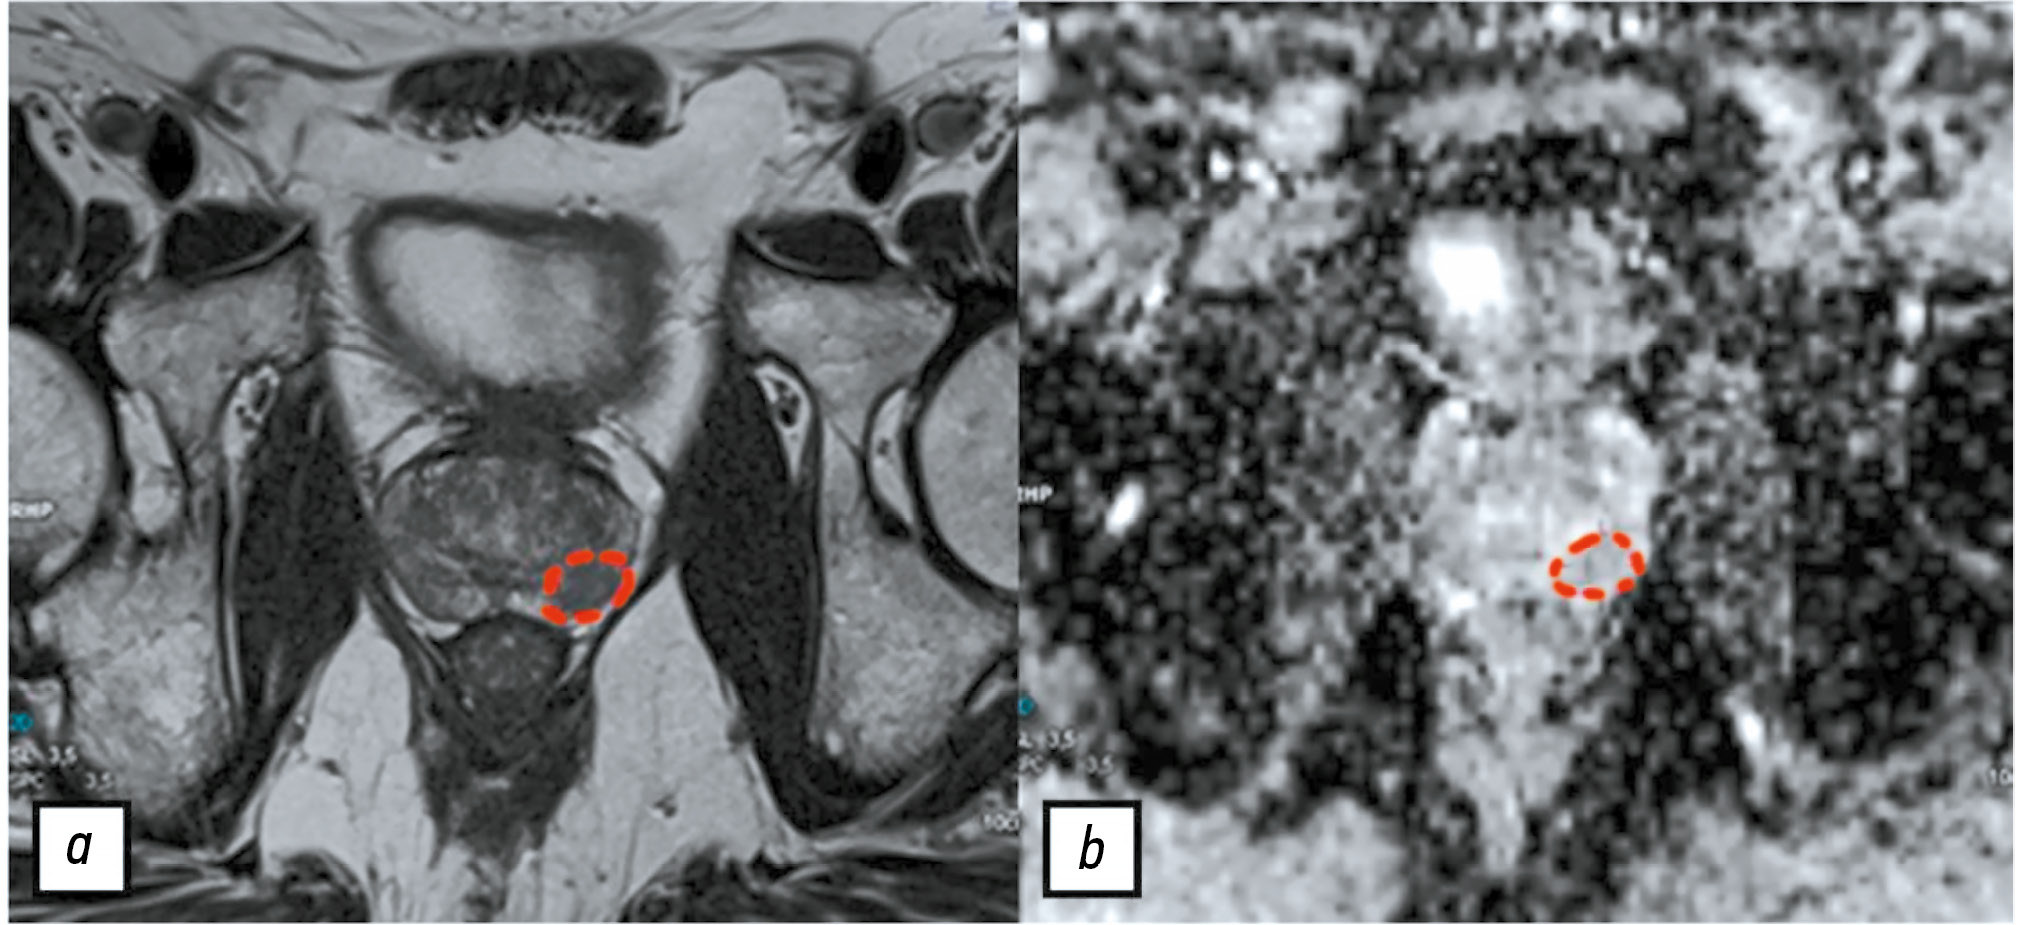

BACKGROUND: Texture analysis improves the diagnostic accuracy of magnetic resonance imaging and differential diagnosis of prostate lesions, which are primarily segmented through manual labeling, resulting in significant inter-expert variability of masks. A consensus-based technique can help reduce inconsistencies in prostate lesion segmentation. However, global scientific studies have not described any standardized, consensus-based labeling protocols.

AIM: This study aimed to develop a consensus algorithm for manual labeling of prostate lesions by several independent experts and evaluate inter-expert consistency in lesion segmentation.

METHODS: This retrospective study included 60 biparametric magnetic resonance imaging scans of the prostate gland performed according to PI-RADS 2.1 technical specification. The scans showed PI-RADS 3, 4, and 5 lesions. Two independent radiologists manually segmented the prostate lesions using 3D Slicer. Then, the resulting masks were compared using the Dice–Sørensen coefficient (DSC). For lesions with DSC ≥ 0.75, the final mask was based on the overlap between the two original masks. Conversely, for lesions with DSC < 0.75, the final mask was determined using the proposed consensus algorithm.

RESULTS: The proposed consensus algorithm significantly increased the DSC values, from 0.61 [0.48; 0.73] for primary labeling to 0.74 [0.62; 0.79] for labeling using the proposed algorithm (p = 0.01).

CONCLUSION: The proposed consensus-based algorithm for labeling prostate lesions using magnetic resonance imaging data is crucial in addressing inadequate approaches to objective segmentation in research and clinical settings.